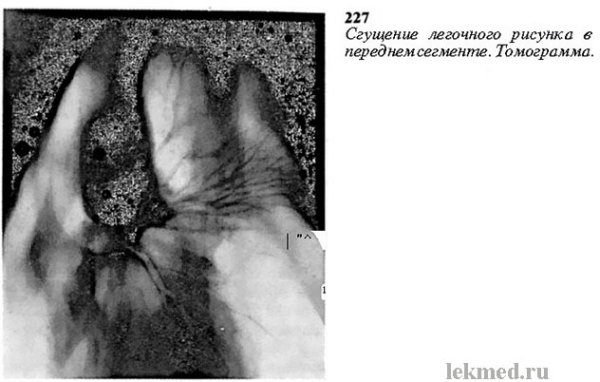

Сгущенный легочный рисунок - это медицинский термин, который описывает изменения визуального образа легких при различных патологиях. При этом наблюдаются уплотнения и затемнения на рентгенограмме или компьютерной томографии легких. Сгущенный рисунок может быть связан с различными заболеваниями, такими как пневмония, хроническая обструктивная болезнь легких (ХОБЛ), рак легкого и другие. Это важный инструмент для диагностики и оценки состояния легких, а также для определения эффективности проводимого лечения.